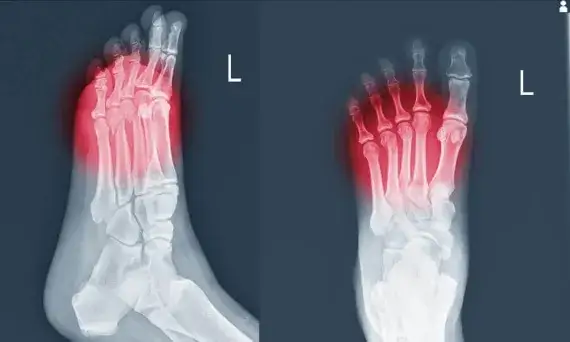

Zrozum, co oznacza ból nóg, jakie są jego przyczyny i objawy. Dowiedz się, kiedy warto szukać pomocy medycznej w przypadku bólu nóg.